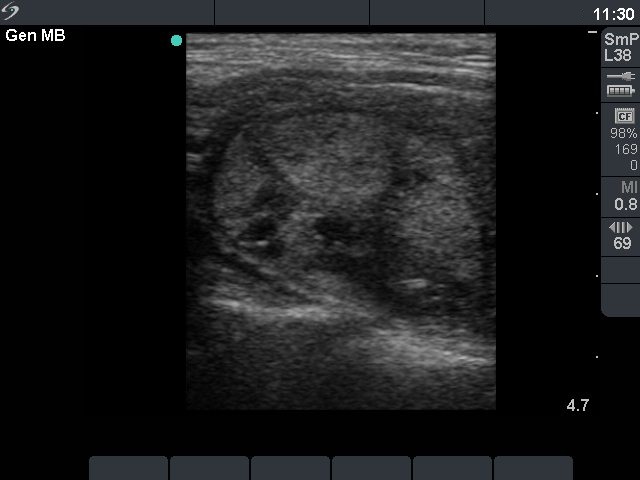

Ultrasonography: The thyroid was moderately hypoechogenic and showed increased vascularity. There was an echonormal nodule in the right lobe with combined perinodular and intranodular vascular pattern.